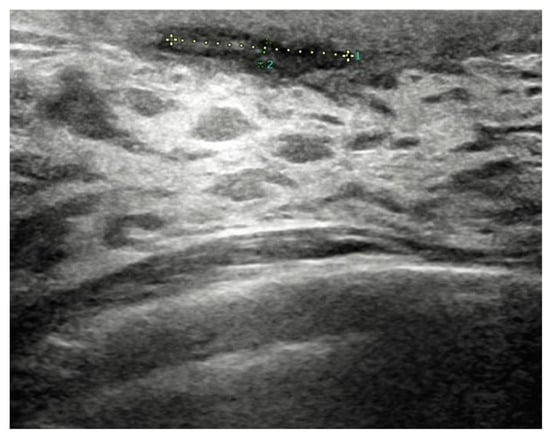

Before surgery, all patients underwent breast ultrasound to assess the presence of an abscess or fistula. Regarding clinical and radiological presentation, 12 patients presented with an abscess in the form of a painful and tender breast mass, with tense and reddened skin but no cutaneous fistula, confirmed by ultrasound (Figure 1, Figure 2 and Figure 3); two patients presented with an abscess associated with periareolar fistula (Figure 4), visible on breast ultrasound; five patients showed signs of a past abscess with negative preoperative ultrasound findings, and among them, one had a fistulous tract without purulent discharge (Table 1). The location of abscesses, fistulas, and their sequelae was the periareolar area in all patients. Additionally, four patients presented with bilateral symptoms. For patients with active abscesses at surgery, the mean size of the abscess cavity was 28.7 mm.

Figure 1. Abscess measuring approximately 16 mm × 2.5 mm in extent, without a liquid component, located in the retroareolar region.